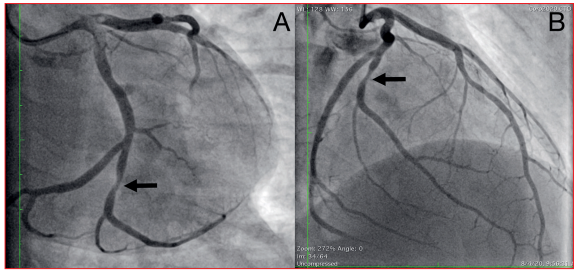

Al quinto día se realizó nueva CACG que constató estenosis residual leve (figura 3) y OCT que observó una reducción considerable de la carga trombótica, con una placa aterosclerótica subyacente que no determinaba una estenosis significativa, y sobre la cual se identificó, como proceso fisiopatológico causante del evento, la disrupción intimal (figura 4). En ausencia de estenosis significativa se decidió no implantar stent y continuar con tratamiento médico con doble antiagregación y anticoagulación.

Figura 3 Coronariografía de control en proyección caudal (A) y caudal derecha (B) donde se observa estenosis residual leve del primer ramo marginal obtuso (flechas).